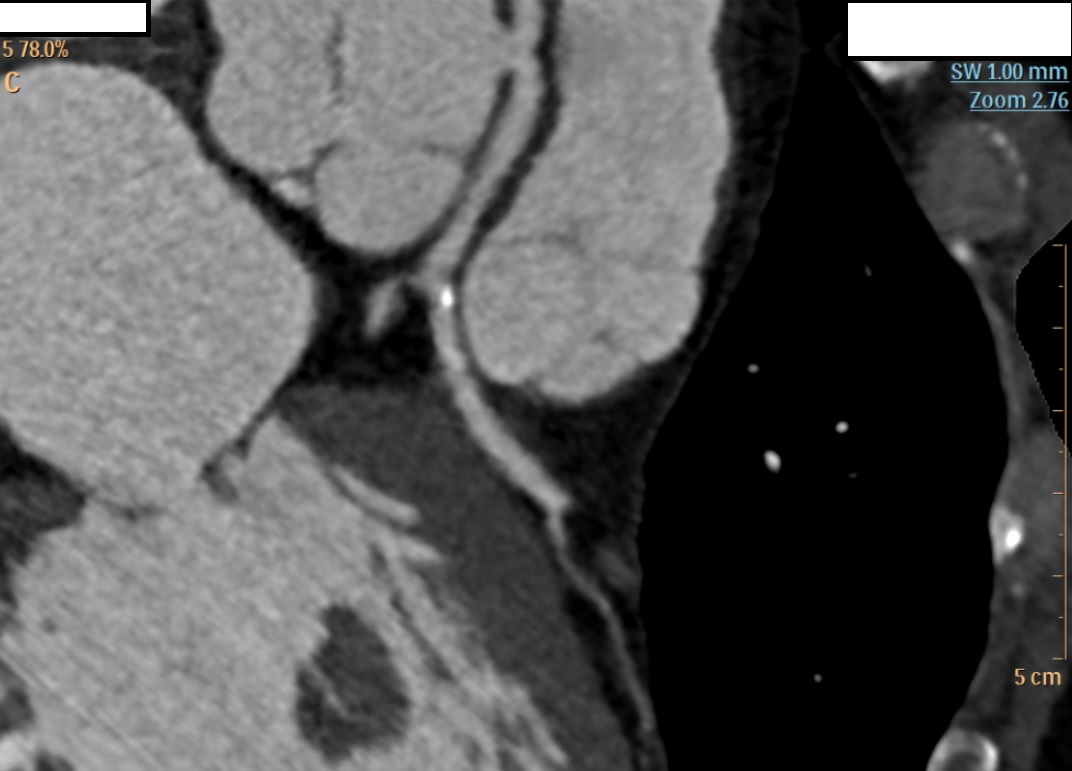

Background Congenital coronary artery anomalies have an estimated prevalence of approximately 1% in the general population. Some "malignant" variants, particularly the anomalous origin of the left coronary artery from the right sinus of Valsalva with an interarterial and/or intramural course, are associated with an increased risk of myocardial ischemia and sudden cardiac death. These anomalies are generally diagnosed at a young age, often during sports medicine screening. Case presentation A 63-year-old man was admitted to the cardiac intensive care unit after a witnessed out-of-hospital cardiac arrest occurring at rest, successfully treated in the pre-hospital setting for ventricular fibrillation with 2 defibrillation shocks and 1 mg of epinephrine. His medical history included treated arterial hypertension and known left bundle branch block (LBBB); occupation: butcher. On admission to the emergency department, electrocardiography showed sinus rhythm with LBBB, severe hypokalemia (K⁺ 2.6 mmol/L), and elevated troponin T (peak 205 ng/L). Transthoracic echocardiography (bad quality) revealed septal dyssynergy and mildly reduced left ventricular ejection fraction. Coronary angiography (CGF) showed no significant coronary stenoses and an ectopic origin of the left coronary artery from a non-coronary sinus, without clear definition of its course. Cardiac magnetic resonance imaging (MRI) was negative for fibrosis, necrosis, or myocarditis. During the diagnostic work-up, suspicious pelvic bone lesions were detected but subsequently ruled out as neoplastic by MRI and PET-CT. To complete the cardiological assessment, coronary computed tomography (CT) demonstrated origin of the left coronary artery from the right coronary sinus, with an acute take-off angle (<45°), a probable short intramural course, and an interarterial course between the aorta and pulmonary artery. Based on these findings, surgical correction with an unroofing procedure was indicated. Conclusions This case represents an atypical presentation of a "malignant" coronary anomaly given the age and mode of onset, occurring at rest in an adult patient. CGF and MRI may be insufficient in the anatomical characterization of coronary anomalies, while coronary CT remains the method of choice for defining the course and therapeutic strategy. Clinical suspicion remains a fundamental element in identifying causes of cardiac arrest that are only apparently idiopathic.